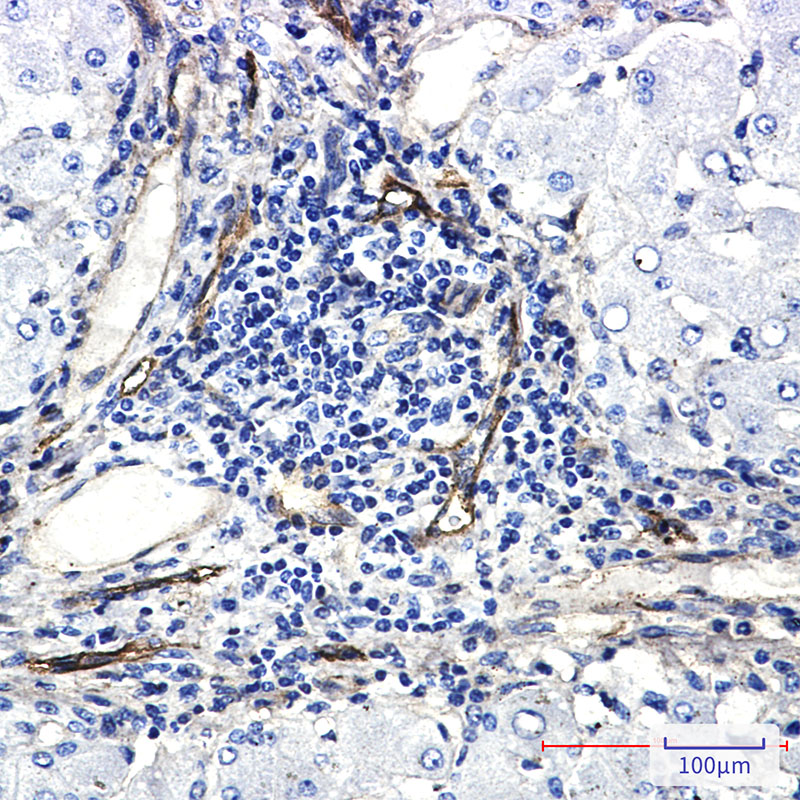

分类: 科研抗体货号: P22544别名: PTK2B; FAK2; PYK2; RAFTK; Protein-tyrosine kinase 2-beta; Calcium-dependent tyrosine kinase; CADTK; Calcium-regulated non-receptor proline-rich tyrosine kinase; Cell adhesion kinase beta; CAK-beta; CAKB; Focal adhesion kinase 2; FADK 2; Pro应用: WB,IP,IHC反应种属: Human